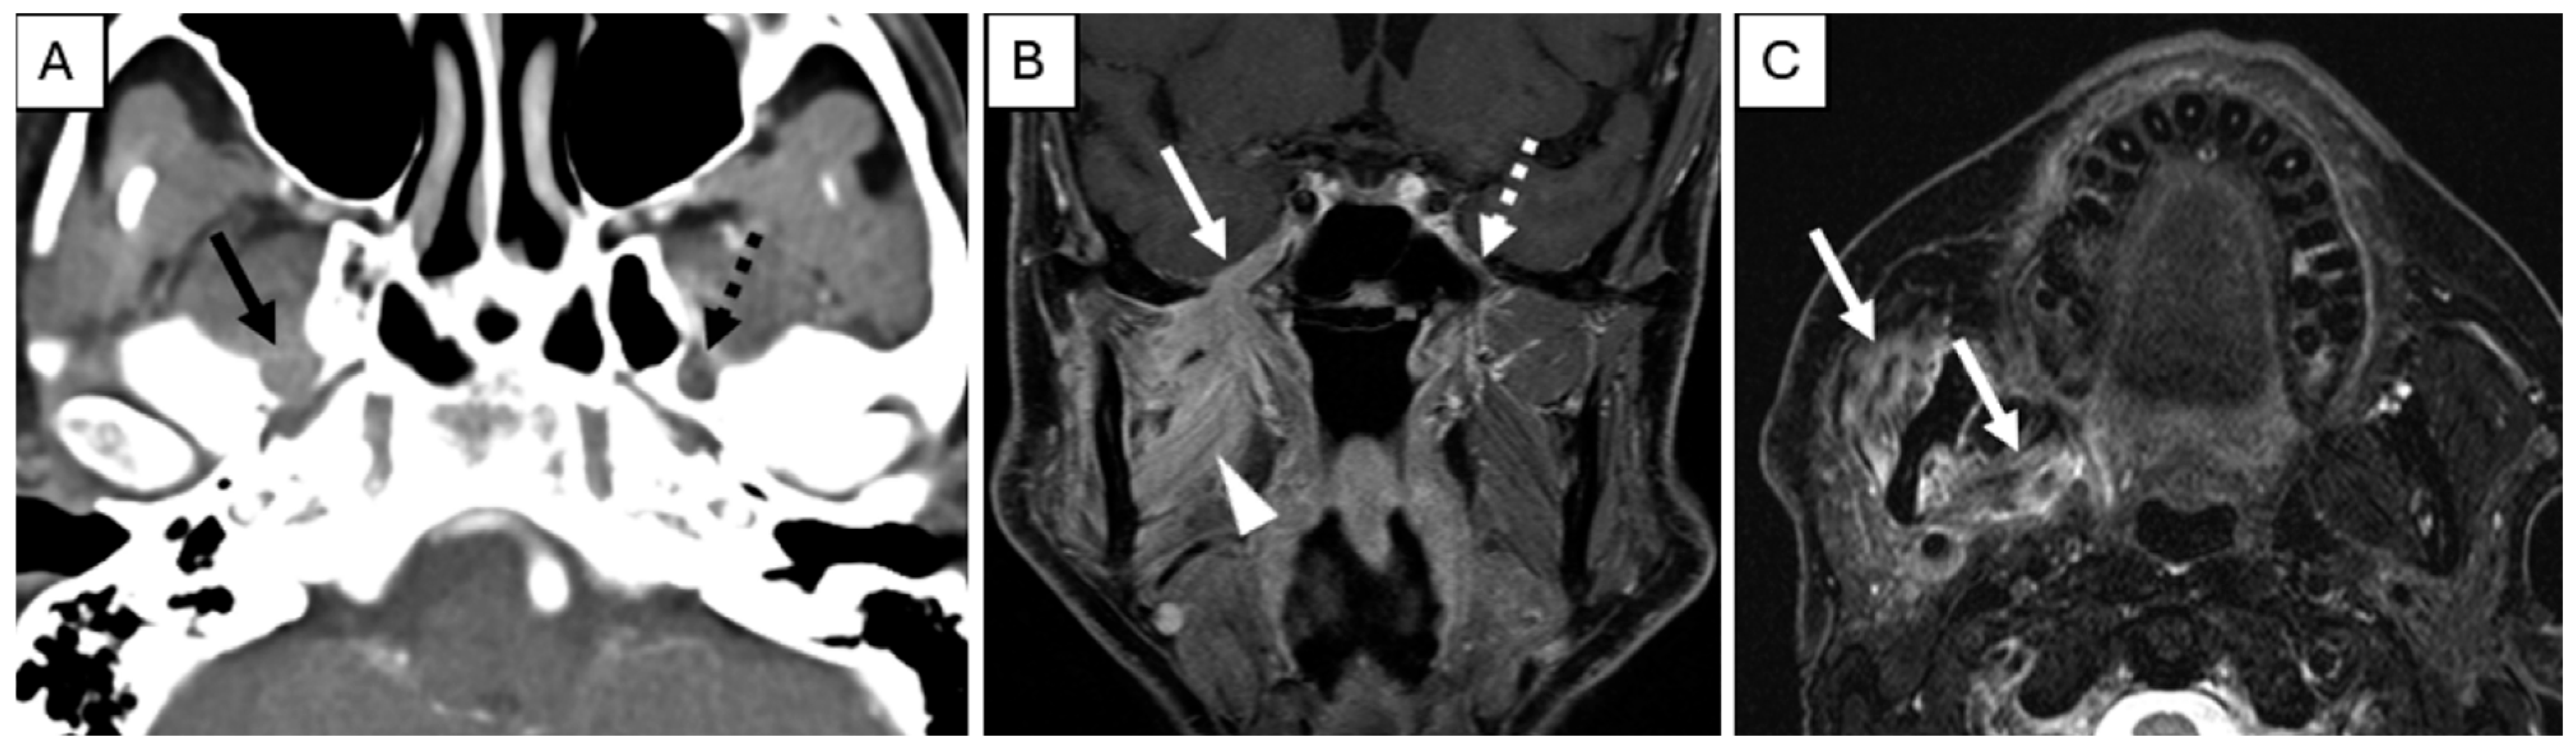

- Overfield, C.J.; Rhyner, P.A.; Hall, M.R.; Bhatt, A.A. More than Skin Deep: Imaging of Dermatologic Disease in the Head and Neck. RadioGraphics 2024, 44, e240052. [Google Scholar] [CrossRef] [PubMed]

- Agarwal, M.; Wangaryattawanich, P.; Rath, T.J. Perineural Tumor Spread in Head and Neck Malignancies. Semin. Roentgenol. 2019, 54, 258–275. [Google Scholar] [CrossRef]

- Paes, F.M.; Singer, A.D.; Checkver, A.N.; Palmquist, R.A.; De La Vega, G.; Sidani, C. Perineural Spread in Head and Neck Malignancies: Clinical Significance and Evaluation with 18F-FDG PET/CT. RadioGraphics 2013, 33, 1717–1736. [Google Scholar] [CrossRef] [PubMed]